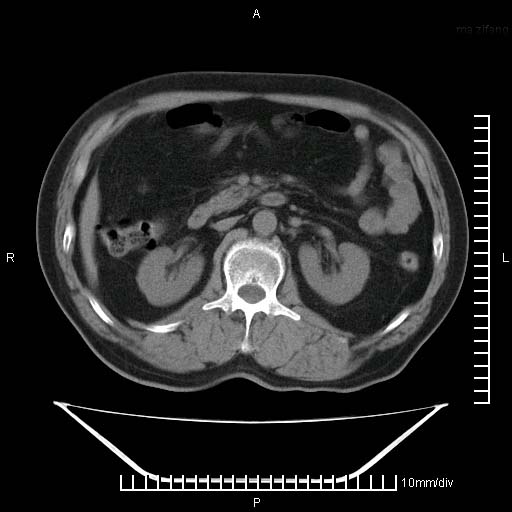

标题: CT25082:肝脏增强:男性,70岁 [打印本页]

标题: CT25082:肝脏增强:男性,70岁

患者以心脏疾病收住院,腹部无明显症状,b超查肝脏有占位。

牛眼征,中心坏死无强化,外缘强化,最外缘又见低密度,考虑转移,与脓肿鉴别

肝内多发转移瘤,右下肺炎症并少量胸水。胃壁增厚建议胃镜,胰尾部“病变”为肠管。

1)肝脏多发性转移瘤(不排除胰尾癌转移所致可能)。2)腹水。3)右侧少量胸腔积液。

右下胸膜肥厚。

胰尾占位?结肠脾曲?

ct25082 结果:转移瘤

外院mr结果:胰尾恶性占位。

肝多发低密度灶;轻度强化,较水密度高,考虑转移,不排除肝脓肿